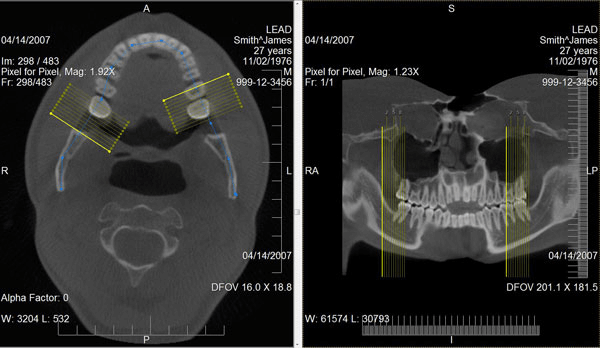

leadtools dicom 技术使开发人员可以轻松的创建dicom应用程序,包括dicom目录(dicomdir)、通信、安全、影像的显示(2d、3d)和处理(图像测量、标注)。同时也支持modality worklist(mwl scu),当病人需要检查时只需要门诊发送mwl请求,放射科室核查无误后进行检查,并支持mpps,这样pacs可以实时查询病人的检查状态。